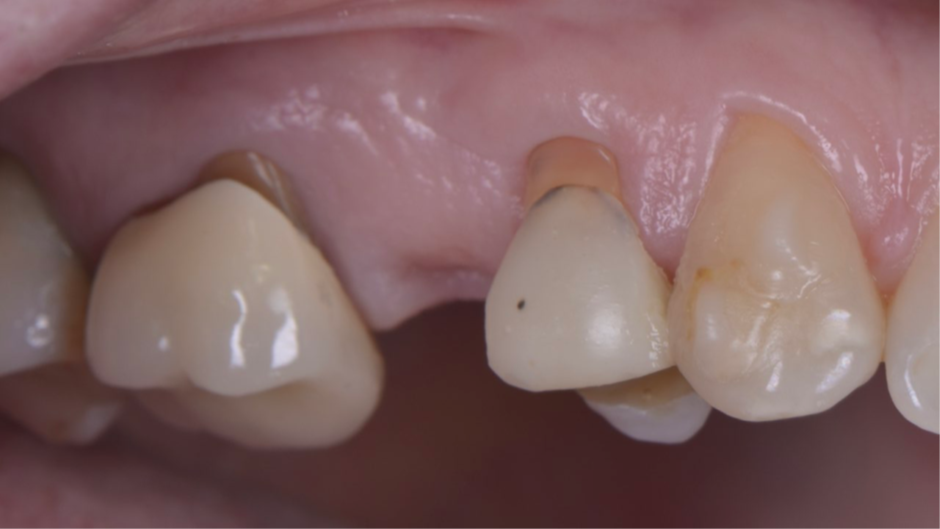

Para fazermos a coroa definitiva, precisamos posicionar a margem gengival semelhante aos dentes adjacentes. Nesse caso, usamos o túnel check de prótese CM para escolha da cinta do pilar (Figura 7). Temos que tomar muito cuidado em saber onde posicionar a margem gengival vestibular da coroa sobre implante, pois quando temos muita espessura de mucosa, a marcação do túnel check pode “confundir” no momento da seleção da cinta do pilar (Figura 8). O pilar de escolha para esse caso foi o Ideale 3.3×4 e foi planejado para ser instalado como uma cinta de 2,5mm, a fim de que a margem da coroa sobre implante fique semelhante à margem dos dentes adjacentes. Então, o pilar Ideale reto 3.3×4 com a cinta de 2,5mm foi instalado (Figura 9) para ser usado como pilar definitivo e fazer uma coroa provisória sobre o implante. A diferença de tamanho entre o diâmetro cervical do dente natural e o encaixe do implante pode resultar em um perfil inadequado da coroa. Se o perfil for subcontornado, não haverá pressão contralateral ou suporte para a mucosa, e as partículas de alimentos podem ficar retidas.

Figura 9 – Pilar Ideale reto 3.3×4 com a cinta de 2,5mm instalado.

A coroa provisória foi fabricada por impressão 3D para criar os mesmos contornos da face vestibular dos dentes adjacentes (Figura 10). Uma coifa provisória de titânio foi parafusada ao pilar ideale para captura da coroa provisória impressa.

Nesse momento, existia uma grande diferença entre o contorno vestibular da coroa provisória e a posição da margem da mucosa (Figura 11). Então, foi utilizado uma resina flow para a captura da coroa provisória (Figura 12). E posteriormente, foi realizada o acabamento e polimento (Figura 13) para termos um excelente perfil de emergência da coroa (Figura 14).